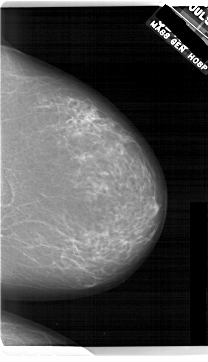

ics_version 1.0 filename A-1743-1 DATE_OF_STUDY 11 7 1996 PATIENT_AGE 69 FILM FILM_TYPE REGULAR DENSITY 3 DATE_DIGITIZED 3 3 1999 DIGITIZER HOWTEK 43.5 SEQUENCE LEFT_CC LINES 6601 PIXELS_PER_LINE 4201 BITS_PER_PIXEL 12 RESOLUTION 43.5 OVERLAY LEFT_MLO LINES 6871 PIXELS_PER_LINE 4516 BITS_PER_PIXEL 12 RESOLUTION 43.5 OVERLAY RIGHT_CC LINES 6871 PIXELS_PER_LINE 3946 BITS_PER_PIXEL 12 RESOLUTION 43.5 NON_OVERLAY RIGHT_MLO LINES 6526 PIXELS_PER_LINE 3811 BITS_PER_PIXEL 12 RESOLUTION 43.5 NON_OVERLAY |